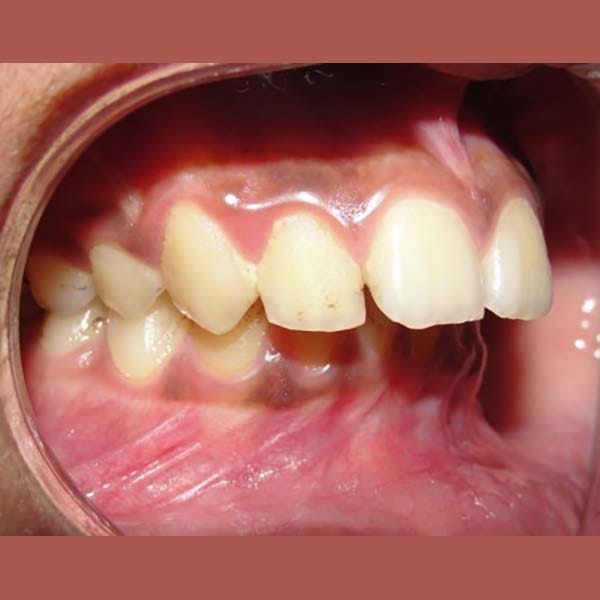

عندما يكون سبب بروز الأسنان هو تراجع الفك السفلي، فإن الحل الأمثل هو التدخل المبكر. بصفتي أخصائي تقويم أسنان في العين، أستخدم الأجهزة الوظيفية لتوجيه النمو. هذه الحالة توضح كيفية علاج بروز الأسنان بالجهاز الوظيفي بنجاح وتأثيره الرائع على ملامح الوجه.

عانى هذا الشاب اليافع من بروز شديد في الأسنان وصل إلى 1 سم، وكان سببه الرئيسي هو تراجع الفك السفلي، وهو ما كان يظهر بوضوح على بروفيل وجهه الجانبي.

كما تظهر الصور، كان التحسن جذرياً ليس فقط في الابتسامة ولكن في تناسق ملامح الوجه بالكامل. تم تصحيح البروز، وتحسنت علاقة الفكين، وحصل الشاب على ابتسامة جميلة وواثقة.